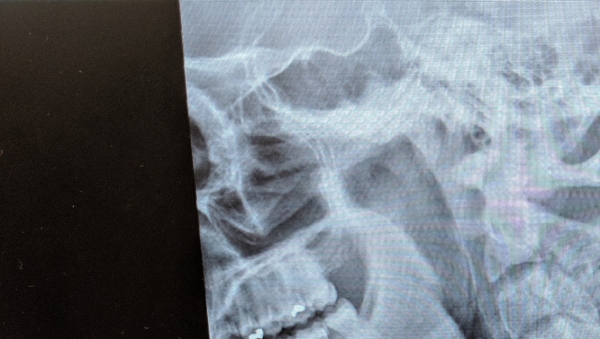

This X-Ray shows the location of Matthew Ewell's spinal injury.

"I landed, dying almost instantly from impact, and crushed my C7 vertebrae, causing paralysis," he told a crowd recently at an Old Dominion University gathering. "I had to be resuscitated twice, flatlining for roughly seven minutes."

Ewell was initially diagnosed with an unrecoverable incomplete spinal cord injury. He was paralyzed from the chest down. His plans for a career in the military would vanish, and his life would change forever.